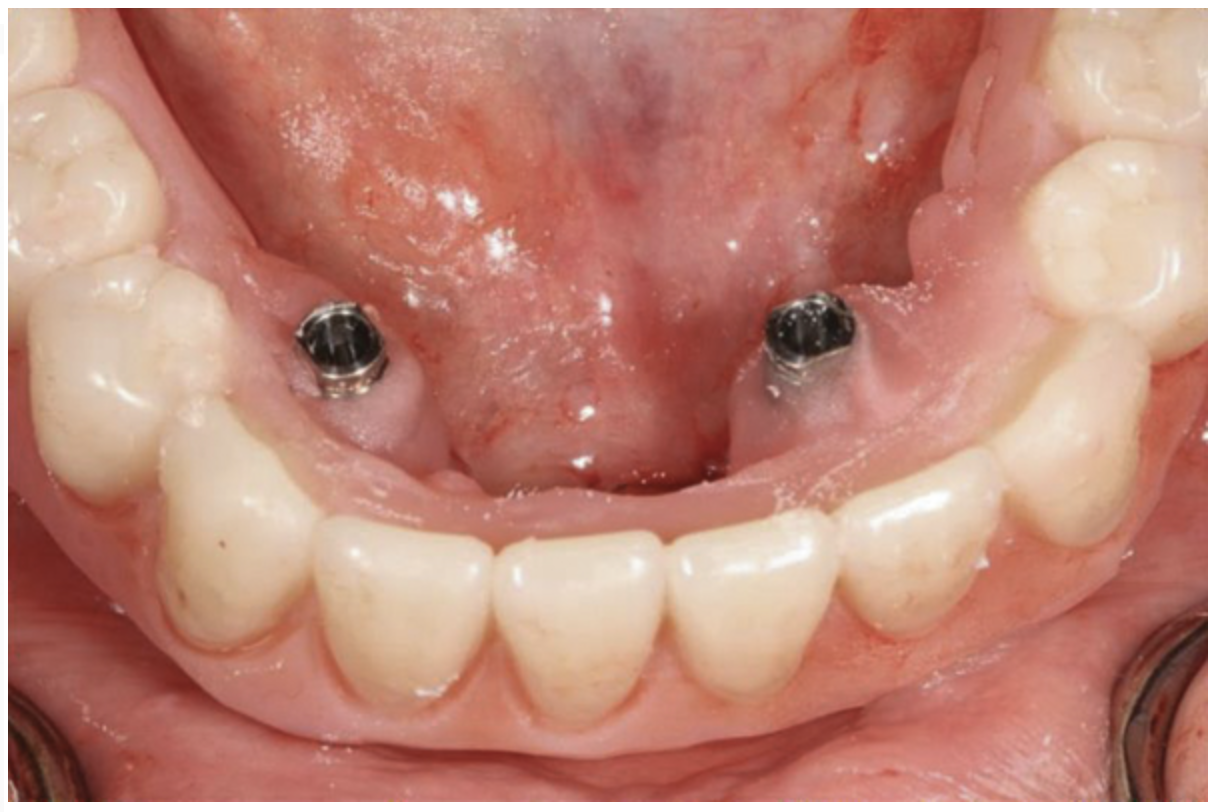

Fig 18. The patient’s intraoral condition.

Figure 18

Fig 20. Patient intraoral condition 3 years following delivery of maxillary and mandibular All-on-4 definitive prosthesis.

Figure 20